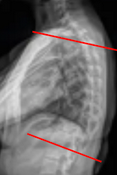

Thoracic Kyphosis (T5–T12 Cobb)

Sagittal Vertical Axis (SVA)

T1 Pelvic Angle (T1PA)

L1 Pelvic Angle (L1PA)

T4 Pelvic Angle (T4PA)

Global Tilt (C7 vertical tilt + pelvic tilt)